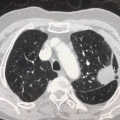

Ο Γεωργιαννάκης Εμμανουήλ είναι Θωρακοχειρουργός με ιατρείο στο Νέο Φάληρο (εντός του Metropolitan Hospital). Είναι απόφοιτος της Ιατρικής Σχολής και έλαβε την ειδικότητα Χειρουργικής Θώρακος από την Κλινική Καρδιοθωρακικής Χειρουργικής του Πανεπιστημιακού Γενικού Νοσοκομείου Αττικόν. Στο πλαίσιο της ειδίκευσής του, εκπαιδεύτηκε στο Ειδικό Αντικαρκινικό Νοσοκομείο Πειραιά "Μεταξά" και στο 417 Νοσηλευτικό Ίδρυμα Μετοχικού Ταμείου Στρατού (ΝΙΜΤΣ). Εξειδικεύτηκε στις Ελάχιστα Επεμβατικές Τεχνικές της Θωρακοχειρουργικής (Θωρακοσκοπικές, Ρομποτικές) στο Shanghai Chest Hospital της Κίνας, το οποίο κατατάσσεται στην πρώτη θέση παγκοσμίως στη Θωρακοχειρουργική. Αξίζει να σημειωθεί ότι είναι ο πρώτος Έλληνας που αποφοίτησε από το εν λόγω ίδρυμα Θωρακοχειρουργικής και τιμήθηκε με τη συνεχιζόμενη διατήρηση του δικαιώματος άσκησης χειρουργικής εκεί. Παράλληλα, μετεκπαιδεύτηκε στη Χειρουργική Καρδιάς και Θώρακος στο St James's University Hospital της Αγγλίας, ενώ πιστοποιήθηκε στο Ρομποτικό Σύστημα Da Vinci στο Institut de Recherche contre les Cancers de l'Appareil Digestif (IRCAD) και διενήργησε την πρώτη Πανελλήνια και Βαλκανική εγχείρηση θώρακος με το εξελιγμένο ρομποτικό σύστημα. Κατόπιν προσκλήσεως, διενήργησε την πρώτη Ρομποτική Θυμεκτομή και την πρώτη Ρομποτική Λοβεκτομή Πνεύμονα στην Κυπριακή Δημοκρατία, στο American Heart Institute της Λευκωσίας. Επιπλέον, πραγματοποίησε την πρώτη Ρομποτική Λοβεκτομή Πνεύμονα στην Ελλάδα και στη Νοτιοανατολική Ευρώπη, πλήρως αναγνωρισμένη από την αμερικανική Intuitive μέσω της ελληνικής αντιπροσώπου Sofmedica. Έχει πραγματοποιήσει πολυάριθμες ρομποτικές επεμβάσεις και θωρακοσκοπήσεις, ενώ συνεχίζει να προάγει τις Ελάχιστα Επεμβατικές Τεχνικές Θωρακοχειρουργικής στην Ελλάδα και το εξωτερικό. Το 2017, οργάνωσε τη σύσταση του νέου Τμήματος Ελάχιστα Επεμβατικής Θωρακοχειρουργικής στο Metropolitan Hospital και έκτοτε διατελεί Διευθυντής του εν λόγω τμήματος, ενώ είναι ο Γενικός Εκπαιδευτής και Πρόκτωρας για τη Ρομποτική Θωρακοχειρουργική για όλη τη Νοτιοανατολική Ευρώπη.